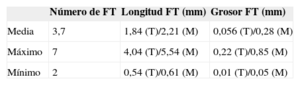

RESULTADOSInvestigación básicaEstudio anatómicoInicialmente se tomaron las medidas básicas de los corazones mostrados en la tabla 1. Los resultados de disección cadavérica de corazones humanos mostraron que los 41 corazones tenían al menos 2 FT. La media de los hallados fue 3,7. Los dividimos según sus características visuales de grosor en los más gruesos, musculares (M), y más delgados, tendinosos (T), que son de menores longitud y grosor (tabla 2).

Resumen de los resultados de falso tendón de la disección cadavérica

| Número de FT | Longitud FT (mm) | Grosor FT (mm) | |

|---|---|---|---|

| Media | 3,7 | 1,84 (T)/2,21 (M) | 0,056 (T)/0,28 (M) |

| Máximo | 7 | 4,04 (T)/5,54 (M) | 0,22 (T)/0,85 (M) |

| Mínimo | 2 | 0,54 (T)/0,61 (M) | 0,01 (T)/0,05 (M) |

FT: falso tendón del ventrículo izquierdo; M: FT de características musculares; T: FT de características tendinosas.

Los resultados mediante disección cadavérica de corazones humanos demuestran que la presencia de FT es la norma sin excepción, con una media de entre 3 y 4 FT encontrados. Esta frecuencia es la mayor de las halladas en estudios previos4, ya que en series cortas de animales se había hallado hasta en un 95%16. La histología, como en estudios anteriores, muestra que están compuestos por fibras de colágeno y musculares en distinta proporción, pero son más frecuentes las fibras musculares en los FT de mayor grosor. Esto ha permitido clasificarlos en 2 grupos: musculares y tendinosos, aunque no se sabe si funcionalmente son distintos. Las tinciones realizadas no permitieron visualizar las estructuras de trasmisión eléctrica, si bien hay estudios que refieren su presencia y su implicación en las arritmias cardiacas19,20,26.